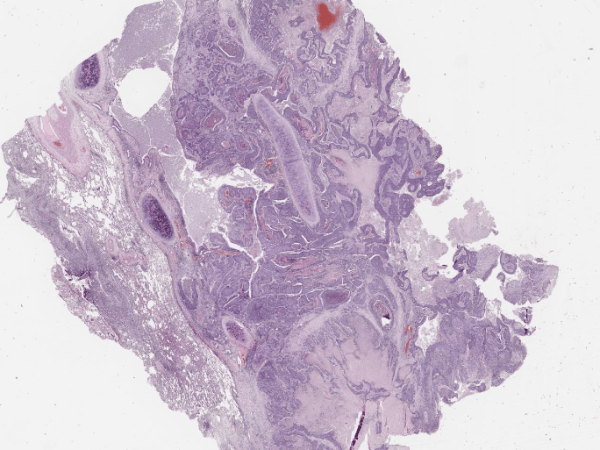

Плоскоклетъчен карцином на бронха

Виждам бял дроб. Отляво е разположен бронх (хиалинен хрущял ), участък с метаплазия, преминаване на едноредния цилиндричния респираторен епител в многослоен плосък и дисплазия. Инфилтрация в стената на бронха от гнезда и повлекла от атипични плоскоепителни клетки, зони на некроза, кератин и стромна реакция. Въпроси? Макроскопски форми на карцинома на белият дроб? – голям прехилусен…